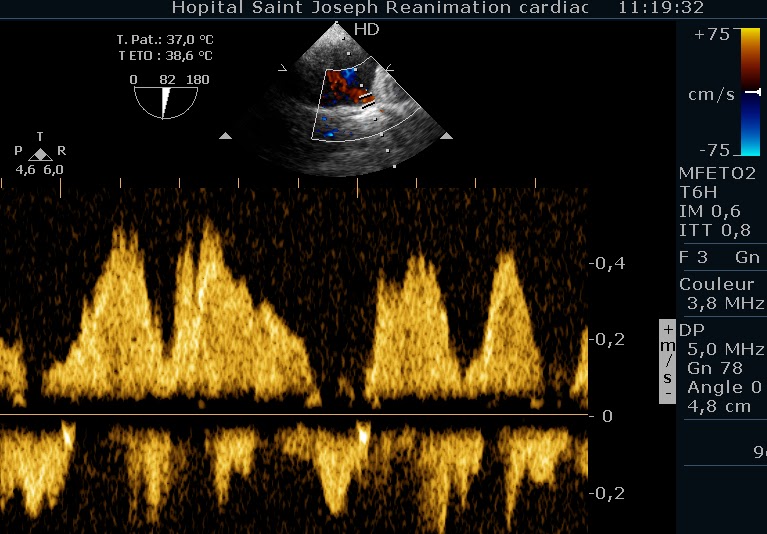

Mais chacun sait qu’on écoute, aux portes (ouah, la blague du siècle! heureusement que vous êtes tous en vacances…), et Madame à un souffle à l’auscultation. Un PDS. (Putain De Souffle). Alors, on redécouvre l’insuffisance mitrale sur prolapsus complexe, avec un jet par prolapsus commissural antérieur, et un prolapsus du feuillet antérieur. En ETO, le reflux systolique est franc dans la veine pulmonaire inférieure droite.

Mais le flux dans les autres veines pulmonaires est normal.